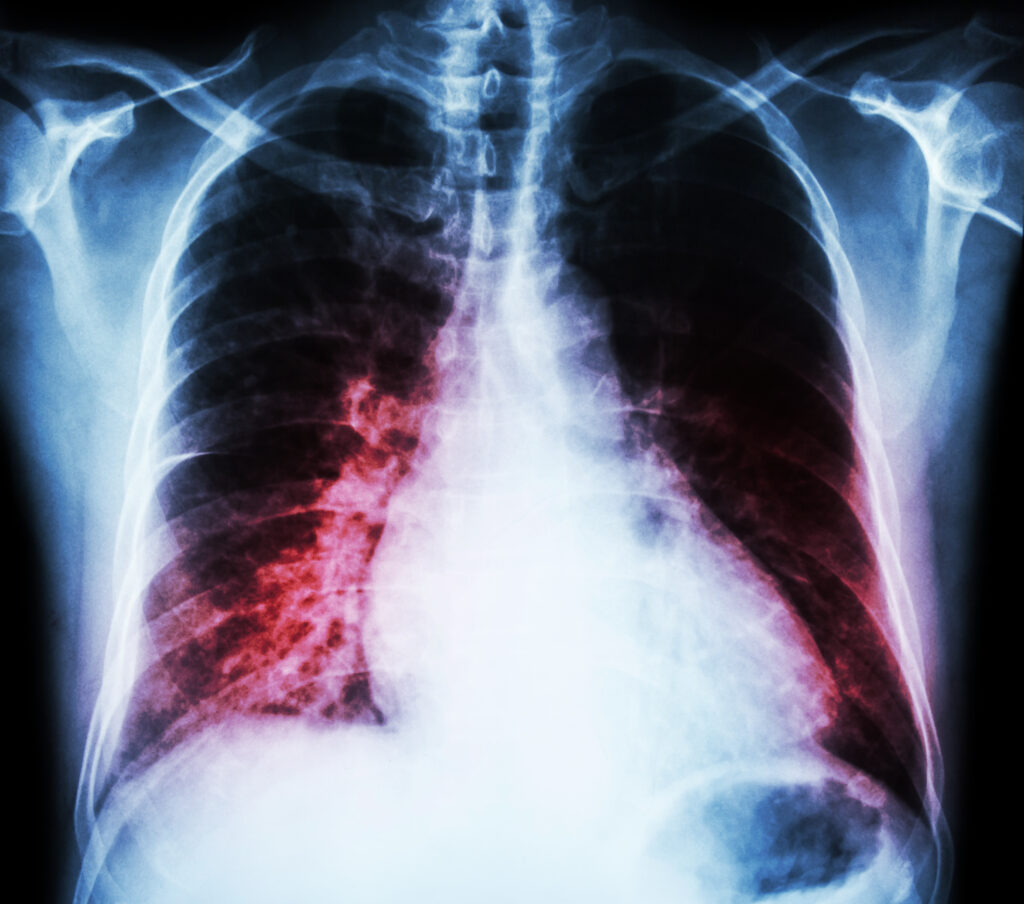

Respiratory failure is one of the most serious respiratory conditions evaluated by the Social Security Administration (SSA). When your lungs can no longer supply enough oxygen to your blood—or remove enough carbon dioxide—your body cannot function normally. Many Texans with respiratory failure experience severe shortness of breath, extreme fatigue, confusion, and repeated hospitalizations. These symptoms often make full‑time work impossible. In these situations, many people need help connecting the dots between respiratory failure and social security disability.

Imaging (X‑ray, CT scans)